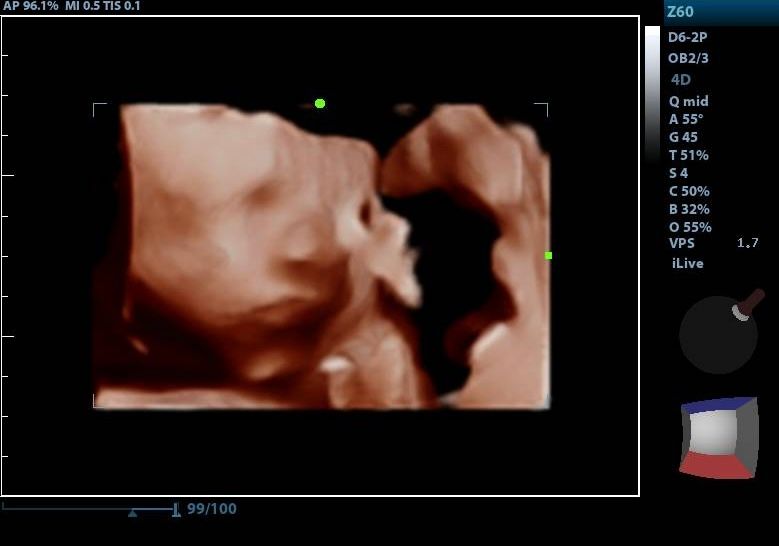

2d, 3d,4d & HD live

At your appointment, we connect directly to your home TV via HDMI, so everyone can enjoy a crystal-clear view. You’ll receive printed keepsake photos in the mail, plus digital images and video recordings delivered straight to your email.

Enjoy a private, affordable ultrasound from the comfort of your home, perfect for moms between 7–41 weeks. Share the moment with loved ones by connecting directly to your TV for real-time viewing in 2D, 3D, or 4D. Ideal for baby showers or gender reveal parties!